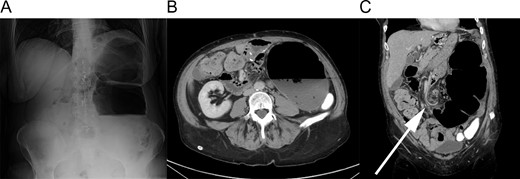

A 55-year-old female with a medical history remarkable for hypertension, chronic pain and cigarette smoking was admitted to the hospital after presenting to the emergency department with several days of worsening abdominal pain, distention and obstipation. She had been evaluated multiple times in prior months for similar symptoms and treated aggressively for constipation. Her surgical history included an open roux-en-y gastric bypass in 2003 resulting in a 140 pound weight loss and an exploratory laparotomy for a perforated gastric ulcer in 2005. Upon admission, she was hemodynamically stable without a leukocytosis. Physical exam revealed left-sided abdominal distention and moderate tenderness. Roentgenogram demonstrated a markedly dilated 14 cm loop of colon in the left upper quadrant concerning for a sigmoid volvulus (Fig. 1A). Subsequent computed tomography (CT) scan showed rectal contrast extending into the transverse colon, mesenteric swirling and a distended cecum, consistent with cecal, rather than sigmoid, volvulus (Fig. 1B and C).

Radiographic findings. (A) Upright plain film showing massive colonic distention. (B) Axial slice of CT scan showing a 14 cm diameter colon. Note the oral contrast filling the descending colon. (C) Coronal slice of CT scan. The arrow indicates mesenteric swirling in the mid-abdomen.